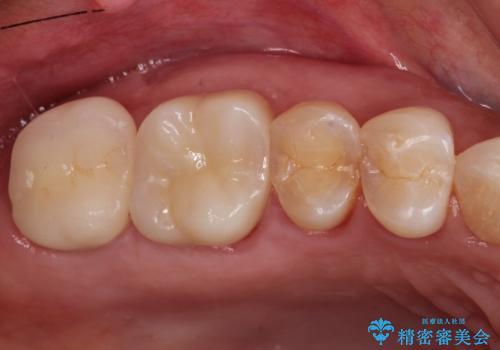

→根管治療完了後、土台を築造し、かぶせ物を製作してかみ合わせを回復する

すでに感染が根の先端まで及んでいたため、かなり強い痛みがありましたが、丁寧に根管治療をすることで内部を可及的に無菌化し、痛みが消失しました。

かぶせ物の種類:Bellezza